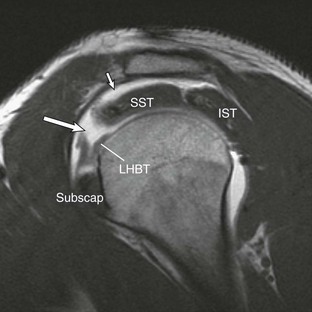

The normal anatomy of the rotator cuff is accurately depicted with MRI. The supraspinatus muscle originates along the posterosuperior portion of the scapula above the level of the scapular spine. A single tendon arises out of the muscle and extends superiorly above the humeral head to insert onto the greater tuberosity of the humeral head. The supraspinatus tendon is best evaluated in the oblique coronal and oblique sagittal MRI planes. The subscapularis is located anteriorly and has multiple tendon slips. It has a broad origin along the anterior aspect of the scapula and attaches to the lesser tuberosity on the anterior aspect of the humeral head. An extension of the subscapularis tendon known as the transverse ligament extends across the intertubercular groove and helps to stabilize the long head of the biceps tendon within the intertubercular groove. The subscapularis muscle and tendon are best evaluated on axial and oblique sagittal MRI. The infraspinatus is located posterosuperiorly and has a broad origin along the posterior aspect of the scapula inferior to the scapular spine. The teres minor is located posteroinferiorly, below the level of the infraspinatus, originating along the axillary surface of the scapula and inserting on the most inferior aspect of the greater tuberosity of the humeral head. The infraspinatus and teres minor are best evaluated on oblique coronal and oblique sagittal images.

Most cuff tears originate in the supraspinatus tendon; however, large tears may extend into either the infraspinatus or subscapularis tendon. Isolated tears, although less common, occasionally occur in either the infraspinatus or subscapularis (Fig. 44-24) tendon. An isolated tear of the infraspinatus tendon is usually associated with the internal impingement syndrome (discussed further in the section on glenohumeral instability).104 An isolated tear of the subscapularis tendon may result from shoulder dislocation or in association with coracohumeral impingement112 and is best demonstrated on axial MRI as high signal traversing the tendon with retraction of the tendon away from its normal attachment site on the lesser tuberosity. An extension of the subscapularis tendon known as the transverse ligament holds the long head of the biceps tendon in the intertubercular groove, and a tear of the subscapularis tendon may result in disruption of the transverse ligament, leading to medial subluxation or dislocation of the long head of the biceps tendon.113 Axial MRI is well suited not only for evaluating the integrity of the subscapularis tendon but also for demonstrating medial subluxation of the biceps tendon out of the intertubercular groove. The biceps tendon may be displaced superficial to the subscapularis tendon, into the subscapularis tendon (Fig. 44-25) or intraarticular (Fig. 44-26).

The rotator interval is a triangular space in the anterosuperior aspect of the rotator cuff that is bordered by the anterior margin of the supraspinatus and the superior margin of the subscapularis muscle. The interval allows passage of the long head of the biceps tendon from an intraarticular to an extraarticular location and plays an important role in glenohumeral stability; it also facilitates normal function of the biceps tendon. The biceps pulley refers to the sling formed by the coracohumeral ligament and superior glenohumeral ligament in the lateral aspect of the rotator interval where the biceps tendon exits the joint.118 Injury or disease of the interval can be associated with altered range of motion of the glenohumeral joint, adhesive capsulitis, and signs of anterior superior impingement119 or degenerative arthropathy. Isolated injuries of the interval can occur or may be associated with tears of the most anterior aspect of the supraspinatus tendon or the superior leading edge of the subscapularis tendon. Baumann et al.120 suggest that isolated lesions to the pulley are more common than originally believed and that progression to involvement of adjacent rotator cuff tendons occurs.

The rotator interval is the gap between the anterior supraspinatus and upper subscapularis tendons. The roof of the rotator interval is formed by the coracohumeral ligament along the bursal surface and the superior glenohumeral ligament along the articular surface. The coracohumeral and superior glenohumeral merge anteriorly and laterally to form the biceps tendon “sling” that is primarily responsible for stability of the long head of the biceps tendon as it transitions from its intraarticular position within the rotator interval to its extraarticular position within the intertubercular groove.121-124

The superior glenohumeral ligament arises from the superior glenoid tubercle adjacent to the origin of the long head of the biceps tendon and courses deep to the coracoid process and the coracohumeral ligament to insert onto the lesser tuberosity of the humeral head and comprises the articular lining of the roof of the rotator interval. A second portion of the superior humeral ligament extending from the anterior superior labrum to the lesser tubercle and the transverse humeral ligament was described by Kask et al.125 Together the coracohumeral and superior glenohumeral ligaments surround and merge anteriorly around the intraarticular biceps tendon. The long head of the biceps tendon originates from the superior glenoid tubercle and then crosses the joint in an oblique fashion, sitting within the rotator interval, and is covered by the coracohumeral and superior glenohumeral ligaments. The long head of the biceps tendon exits the joint at the level of the intertubercular groove where it is completely covered and stabilized by these two ligaments. At this point, the combination of the medial limb of the coracohumeral ligament and superior glenohumeral ligament acts as a sling to prevent medial subluxation of the long head of the biceps tendon as it exits the joint. The rotator interval is best visualized and evaluated for disease in the oblique sagittal plane, especially when the joint is distended either by a joint effusion or by intraarticular contrast. Schaeffeler et al.126 reported improved sensitivity for biceps pulley lesions by evaluating the biceps tendon for displacement relative to the subscapularis tendon with MRA.

The normal course of the tendon begins as the tendon arises from the long head of the biceps muscle in the upper arm. The tendon then courses through the intertubercular sulcus, located between the lesser and greater tuberosities. As it passes through the intertubercular sulcus, it is held in place inferiorly by the tendon of the pectoralis major muscle as it attaches to the proximal humeral shaft. At the intertubercular groove, it is held in place by the transverse ligament, which is an extension of the subscapularis tendon. Superiorly, it becomes intraarticular, being located in the rotator interval and covered by the coracohumeral ligament and finally by the superior glenohumeral ligament. These two ligaments form the “sling” or pulley mechanism responsible for the stability of the biceps tendon as it transitions from its intraarticular to its extraarticular location.121,128 It then has a broad triangular attachment to the superior labrum at or near the superior glenoid tubercle.